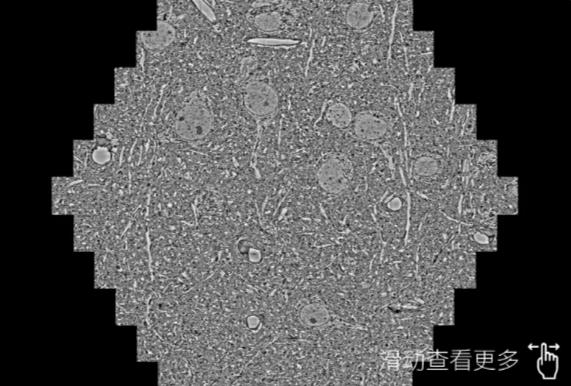

鼠脑切片。左图使用蔡司扫描电镜MultiSEM706对165μmx143pm面积区域成像,耗时仅需1.5秒。右图为鼠脑切片中30μm区域放大效果。样品由芝加哥大学B.Kasthuri提供。